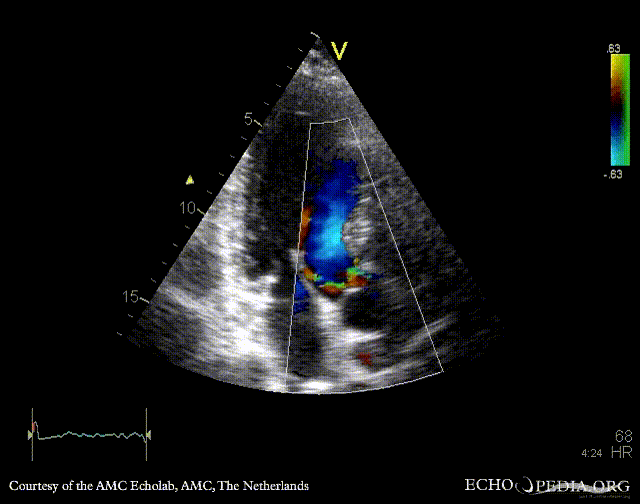

E00418.gif E00419.gif

PLAX: Color Doppler, moderate aortic regurgitation PSAX